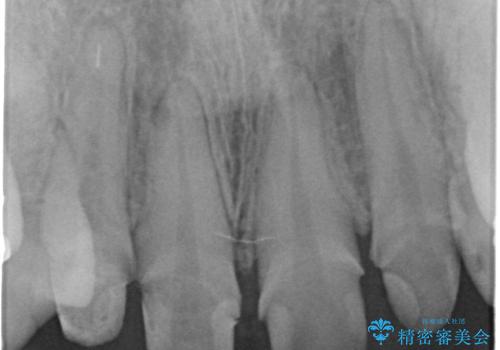

- 神経をとった前歯の変色や、前歯の充填物の変色が大きくなってきたので審美性の改善を求めて来院されました。

充填物や充填物下に再発した虫歯を丁寧に除去し、セラミッククラウンによる審美性の改善、虫歯治療を計画します。